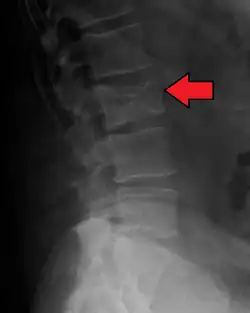

The diagnostic examination of a person with suspected multiple myeloma typically includes a skeletal survey. This is a series of X-rays of the skull, axial skeleton, and proximal long bones. Myeloma activity sometimes appears as "lytic lesions" (with local disappearance of normal bone due to resorption) or as "punched-out lesions" on the skull X-ray ("raindrop skull"). Lesions may also be sclerotic, which is seen as radiodense.[76] Overall, the radiodensity of myeloma is between −30 and 120 Hounsfield units (HU).[77] Magnetic resonance imaging is more sensitive than simple X-rays in the detection of lytic lesions. An MRI may supersede a skeletal survey, especially when vertebral disease is suspected. Occasionally, a CT scan is performed to measure the size of soft-tissue plasmacytomas. Nuclear Medicine Bone scans are typically not of any additional value in the workup of people with myeloma (no new bone formation; lytic lesions not well visualized on nuclear bone scan).

Pathological fracture of the lumbar spine due to multiple myeloma -